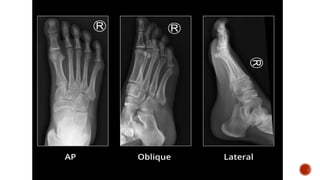

 Foot radiographic views

 Dorsoplantar radiograph of the foot shows destruction of the head of the 5th

metatarsal and the base of the proximal phalanx of the 5th toe with apparant

widening of teh joint space.

 Foot radiograph :

 Dorsoplantar: metatarsals in neutral position

 Medial: DP projection with the foot angled 30-40° medially

 Lateral

 Weight bearing